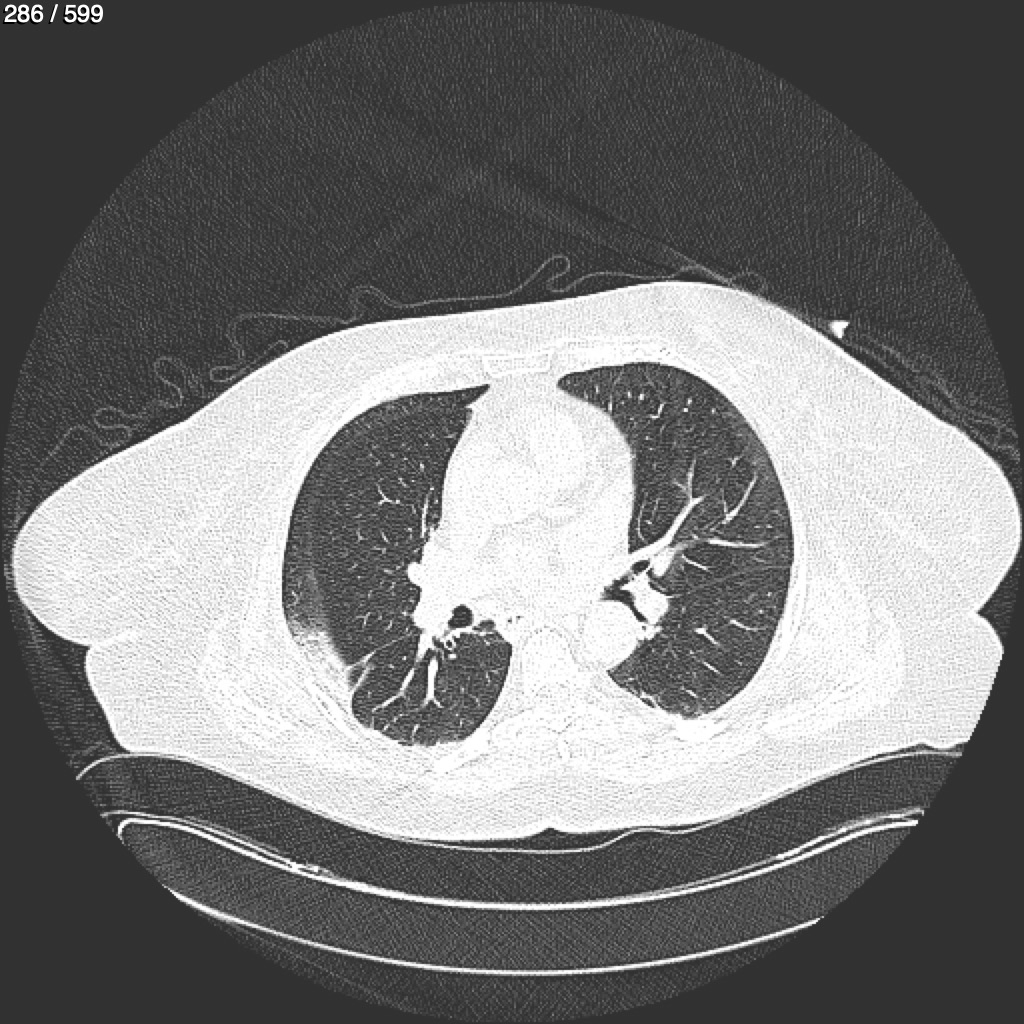

Home G​l​o​r​i​a​ ​G​l​a​d​y​s​ ​B​e​a​s​l​e​y​ ​-​ ​T​ó​r​a​x​ ​T​o​r​a​x​_​S​i​m​p​l​e​ ​(​A​d​u​l​t​o​)